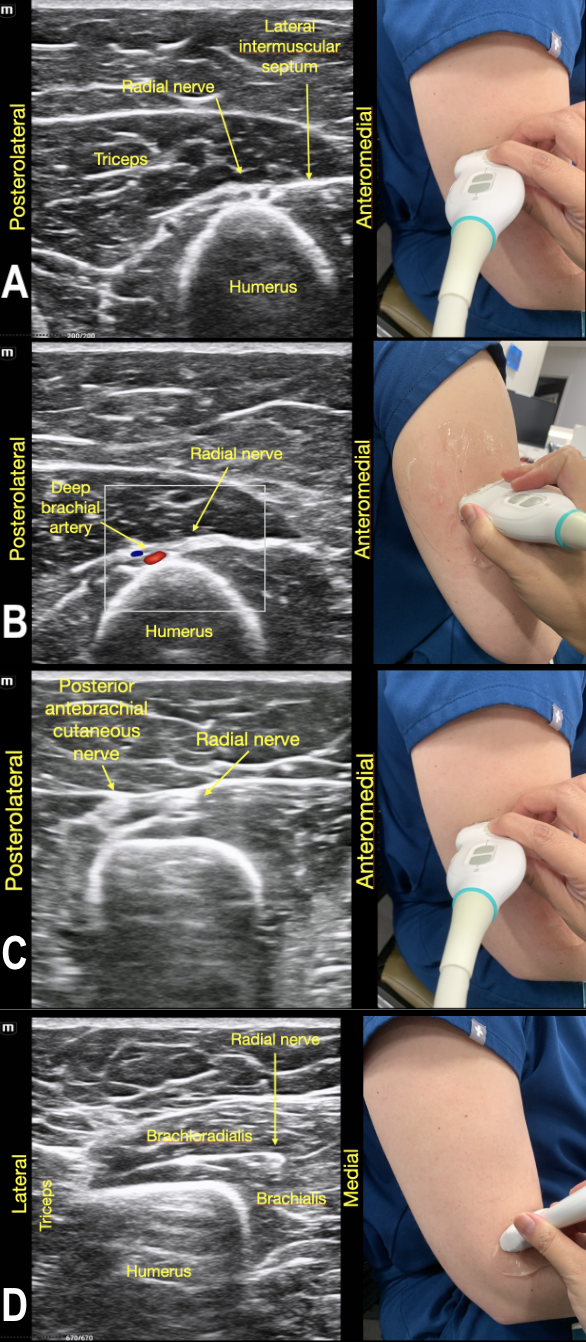

Step by step tracing of the radial nerve from mid-humerus to supracondylar level:

To identify the radial nerve in the mid-humerus position, have the patient in a seated position with the arm extended or held over the abdomen with the elbow flexed. Start with the probe placed transverse across the posterolateral mid-humerus and identify the radial nerve as a hyperechoic honeycombed structure lying directly on top of the humerus. At this point the radial nerve lies within the spiral groove and is also seen adjacent to the deep brachial artery. (Figure 7A)

Branches off the radial nerve that occur within the spiral groove from proximal to distal include: the posterior cutaneous nerve of the arm, motor branch to the lateral head of the triceps, motor branch to the medial head of the triceps and anconeus muscles, lower lateral cutaneous nerve of the arm, and the posterior cutaneous nerve of the forearm. The sensory distribution of these nerves in addition to the superficial branch of the radial nerve occurring below the elbow crease can be seen in Figure 7B. The osteotome distribution of the radial nerve and its branches is seen in Figure 7C.

As the probe is moved distally along the spiral groove, the posterior cutaneous nerve of the forearm can be seen branching from the radial nerve just prior to the lateral intermuscular septum (Figure 7D). In Video Clip 1, the radial nerve passes from the triceps into the biceps through the linear echogenic lateral intermuscular septum, which is a hyperechoic connective tissue layer separating the dorsal and anterior compartment of the arm.13

RadialNerve-Image7 Aug2024.pngFigure 7. The Radial Nerve in its trajectory proximal to distal.